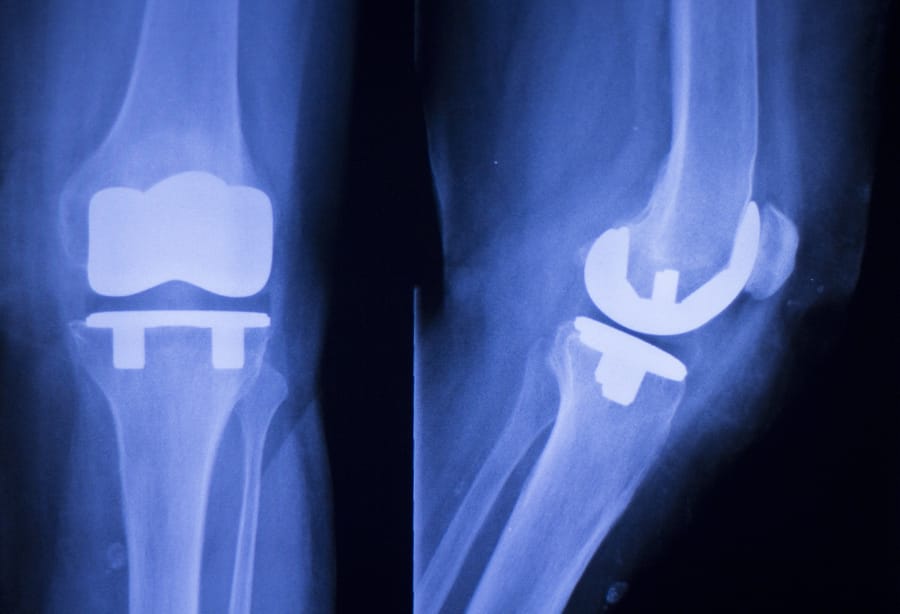

On estime que 4,4 millions d'Américains comptent actuellement sur des implants artificiels du genou. Ces implants peuvent être utilisés pour améliorer la mobilité et la fonction articulaire, en particulier chez les personnes âgées. Le remplacement du genou est l'une des procédures médicales les plus courantes aux États-Unis, et le système de remplacement du genou DePuy a été l'une des options les plus populaires. Cependant, après qu'un problème connu avec le ressort balseal ait été mis au jour, DePuy a rappelé des composants du Dispositif de remplacement du genou Attune en 2015. Les complications d'une arthroplastie du genou DePuy ou d'un implant similaire ont obligé les patients à subir une chirurgie de révision pour résoudre le problème. Le système de remplacement du genou DePuy est une option d'implant de genou populaire aux États-Unis. Cependant, bien que le remplacement du genou DePuy ait été conçu pour réduire le temps nécessaire à la récupération, il a malheureusement été lié à des problèmes graves qui peuvent avoir des effets durables.

Bien que ces dispositifs d'implant du genou soient censés durer de nombreuses années, certains patients affirment qu'ils ont subi une défaillance d'un composant ou d'un dispositif seulement quelques années après la chirurgie initiale de remplacement du genou. Le DePuy Attune n'est pas le seul système d'implant de genou sous le feu des pièces ou des défaillances de l'appareil et d'autres problèmes. D'autres dispositifs de remplacement du genou ont également été associés à des affections et c'est quelque chose qui ne peut plus être ignoré. Lorsqu'une greffe de genou échoue, les résultats peuvent être dévastateurs pour le patient.